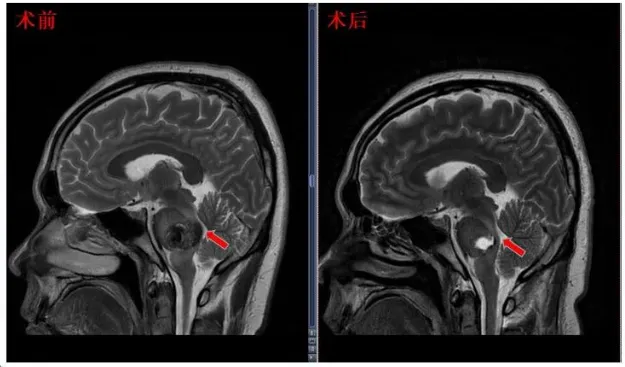

“近期的MRI截图。他们显示了一个很好的发现,完全切除海绵状瘤而不损害周围的脑干结构。不能再好了!”术后4个月,31岁的陈先生在INC巴教授的例行随访中,再次得到这样的好消息。而在随访视频中,陈先生现在已经能走能跑,看起来和正常人无异。

▼术前术后影像对比